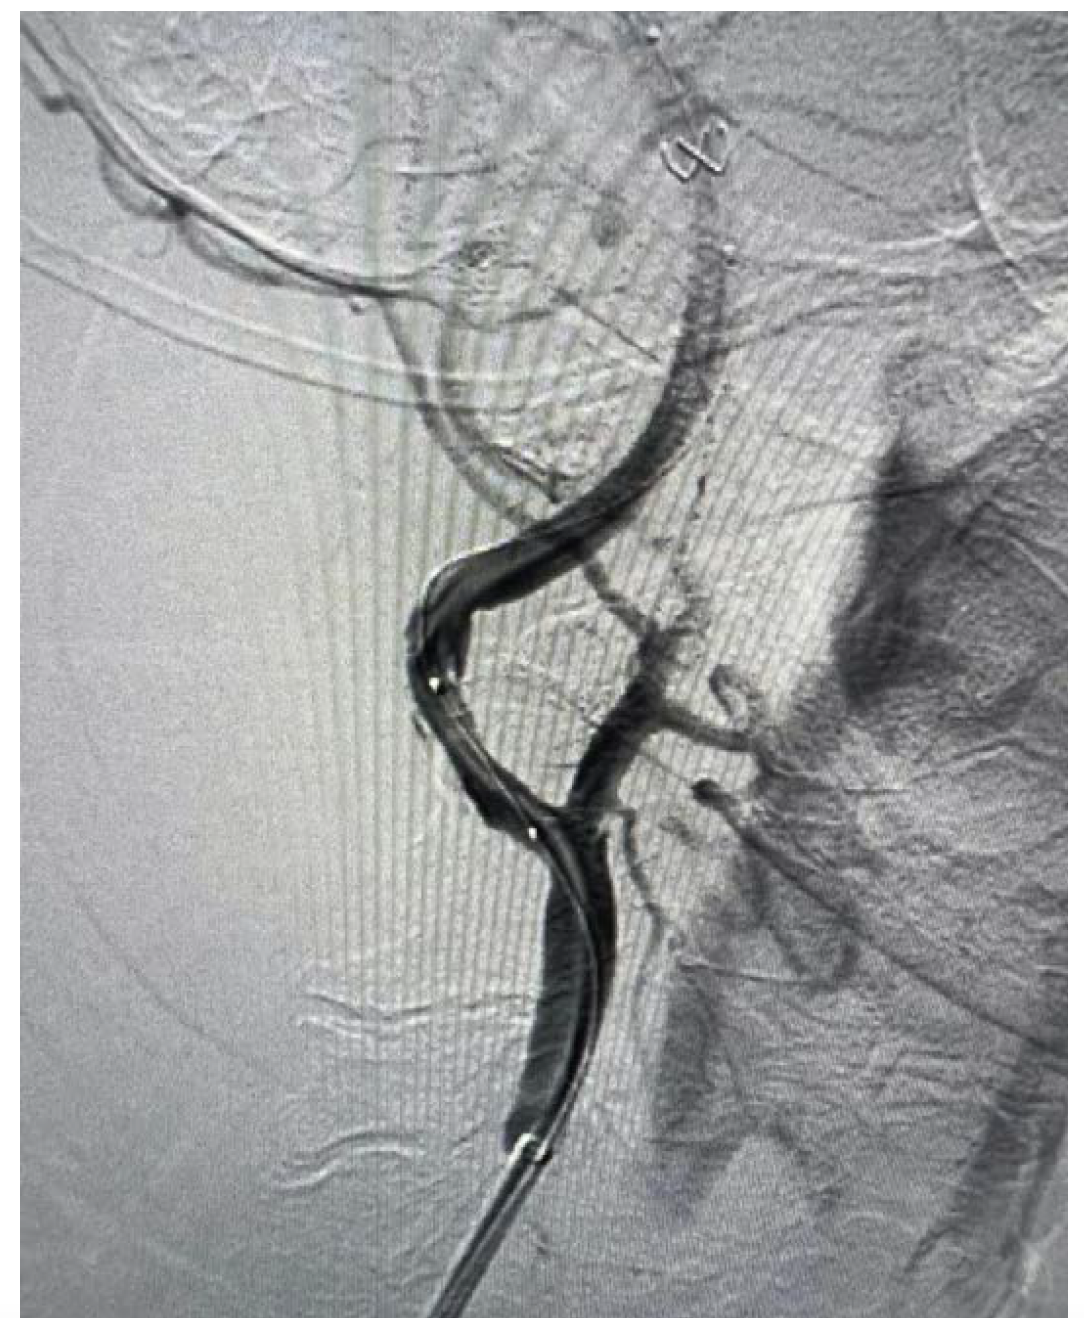

The patient underwent elective carotid stenting as a staged procedure prior to transcatheter aortic valve replacement (TAVR). Her previous diagnostic study utilized right radial artery access but it was difficult to perform selective carotid angiography, specifically that of the left carotid artery.5 Consequently, this intervention was performed from the right groin. A VTK catheter (Cook Medical) was placed in the right common carotid artery, followed by a TAD guidewire (Abbott Vascular) and then a Flexor Shuttle sheath (Cook Medical) with no difficulty. There was no difficulty deploying a large filter wire (NAV RX 7.2 mm, Abbott Vascular), and we were able to dilate with a 4-mm x 15-mm balloon (Abbott Vascular). However, we could not pass a 6/8 self-expanding stent (Abbott) (Figure 1). We performed further predilation with a 6-mm x 15-mm balloon, but we were still not able to pass the 6/8 stent. Because we had already performed adequate predilation, we attempted to pass a 2-cm self-expanding stent (Abbott Vascular) but were still unable to cross the lesion. Finally, we performed predilation balloon angioplasty with a 7-mm x 15-mm balloon (Abbott Vascular), which ultimately allowed us to pass the 6/8 self-expanding stent. After deployment, we removed the filter and a subsequent arteriogram confirmed that the lesion had completely resolved (Figure 2). The patient had no hypotension or bradycardia during the procedure and was discharged the following day. She will undergo TAVR at a later date. This case exemplifies using stepwise predilation of a severely calcified carotid lesion, demonstrating an option for operators.